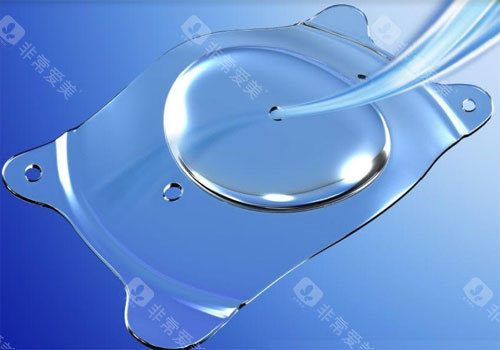

ICL晶体植入手术作为高度近视矫正的主流方案,凭借其可逆性、不损伤角膜的特点,成为越来越多近视患者的选择。

不损伤角膜:适合角膜薄、干眼症等激光手术禁忌人群。

可逆性强:晶体可随时取出,不影响未来其他治疗。

改善比较快:术后24小时即可正常用眼,3天稳定。

视觉质量高:尤其适合较高高度近视(>1000度)患者。